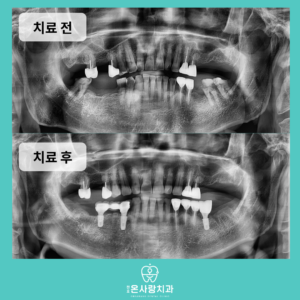

천호동치과, 환자의 상황을 고려한 치아 기능 회복

천호동치과, 환자의 상황을 고려한 치아 기능 회복 우리가 음식을 즐겁게 먹고 건강한 일상을 유지하기 위해서는 치아의 역할이 무엇보다 중요합니다. 치아는 단순히 음식을 자르고 부수는 기능을 넘어 발음을 또렷하게 하고…